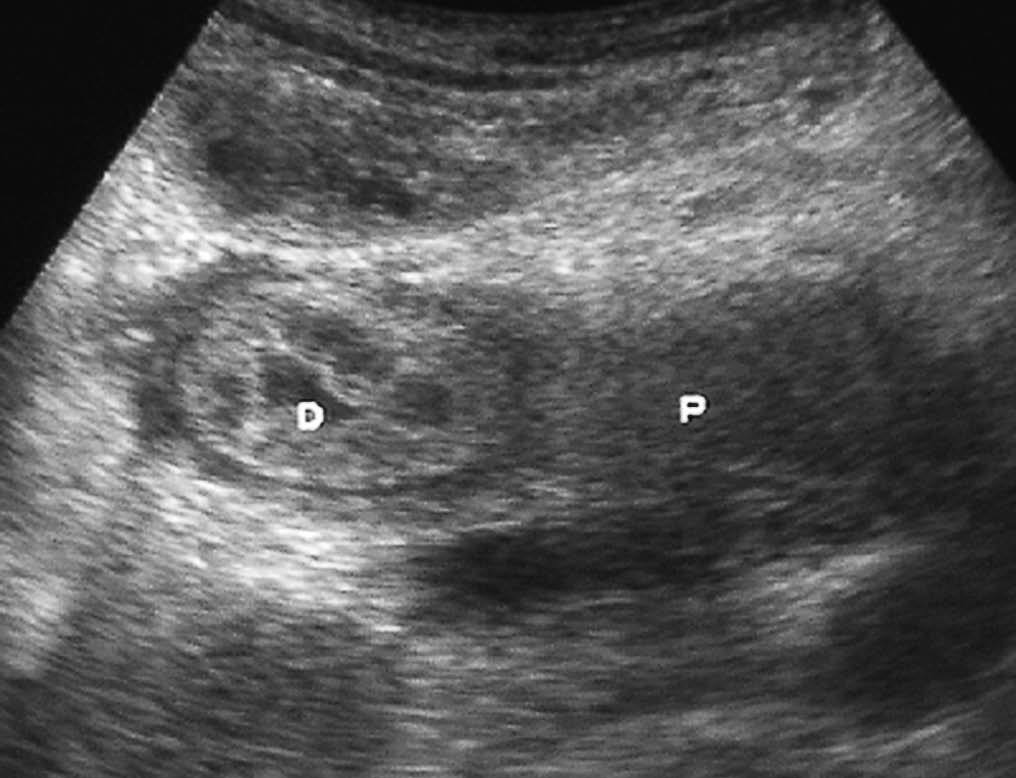

El duodeno también puede verse afectado tanto por extensión de tumores vecinos, siendo los más frecuentes los de estómago, como por neoplasias de colon transverso, páncreas (fig. 21), vesícula, hígado y riñón derecho1,2 (fig. 22).

Fig. 21--Neoplasia de páncreas. (A) Corte transversal de ecografía en el que se aprecia masa pancreática (P) que infiltra la pared duodenal (D). (B) Tomografía computarizada con contraste intravenoso correspondiente, donde se puede observar dilatación gástrica por la obstrucción.